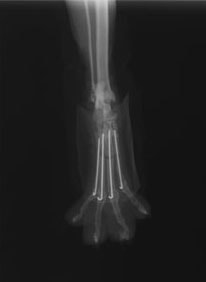

症例3:キルシュナーワイヤーのピンニングによる整復

ペルシャ猫 11ヶ月齢 雄

他院にて左大腿骨遠位の成長板骨折(salter-harrisⅠ型)が認められており、治療相談を目的として来院。当院にて、キルシュナーワイヤーを用いたピンニングにより骨折部位の整復を行いました。術後の経過は良好で、現在も経過観察中です。

術前レントゲン

術後レントゲン

Arthrex社のターゲティングデバイスを用いてピンニングの位置を調整することで、確実な固定を行っています。当院ではこの手術器具以外にも、人の手術にも使用される様々な器具を導入し、手術精度を高め、また医療メーカーと新しい器具の開発、試作にも取り組んでおります。